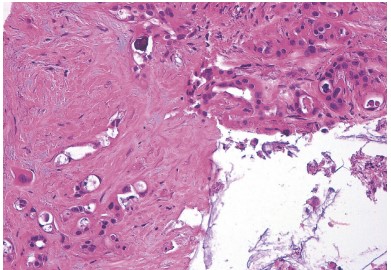

Esophageal Varices (Varicosities): Causes, Warning Signs & Treatment in Karachi Liver Health

Swollen veins in the food pipe (esophageal varices) can burst and cause life-threatening bleeding. Learn the causes, early warning signs, and treatment options available in Karachi.